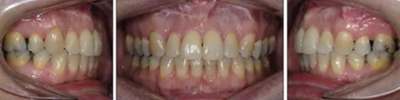

患者曾行正畸治療,現(xiàn)覺(jué)笑容不美觀前來(lái)就診。患者正面觀及側(cè)貌示下頜發(fā)育不足,偏高角,唇閉合不全。上下頜中線齊。覆合、覆蓋4毫米。磨牙關(guān)系及尖牙關(guān)系II類(lèi)。上頜擁擠度4mm,下頜擁擠度6mm。4顆第一前磨牙在第一次正畸治療時(shí)已拔除。上下牙弓呈尖圓型,牙弓狹窄。

患者側(cè)貌改善,下唇唇肌緊張消失,上下唇可自然閉合。磨牙及尖牙關(guān)系糾正至I類(lèi),覆合覆蓋正常。上下頜弓型糾正至卵圓形,牙弓寬度增加。頭影測(cè)量分析示SNA角81.8°,ANB角3°。頭影測(cè)量重疊圖示下頜骨向后旋轉(zhuǎn),垂直面高度略有增加。